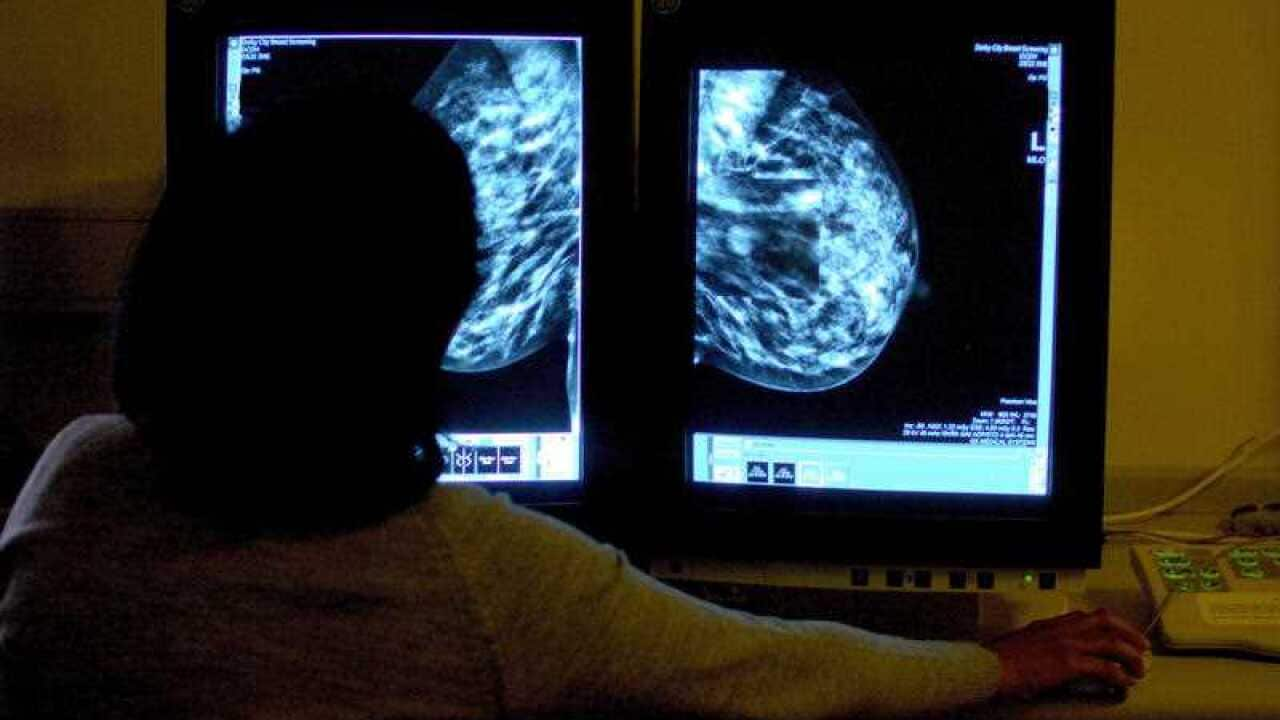

নেহা কুমারের মা রেণু ২০১৪ সালে স্তন ক্যানসারের তৃতীয় ধাপ (স্টেজ ৩) ধরা পড়েন।

তিনি বলেন, তার মা উপসর্গগুলিকে অগ্রাহ্য করেছিলেন এবং অনেক দেরি করে ফেলেছিলেন।

চিকিৎসা নেওয়ার এক বছর পর, ২০১৫ সালে, রেণু মারা যান।